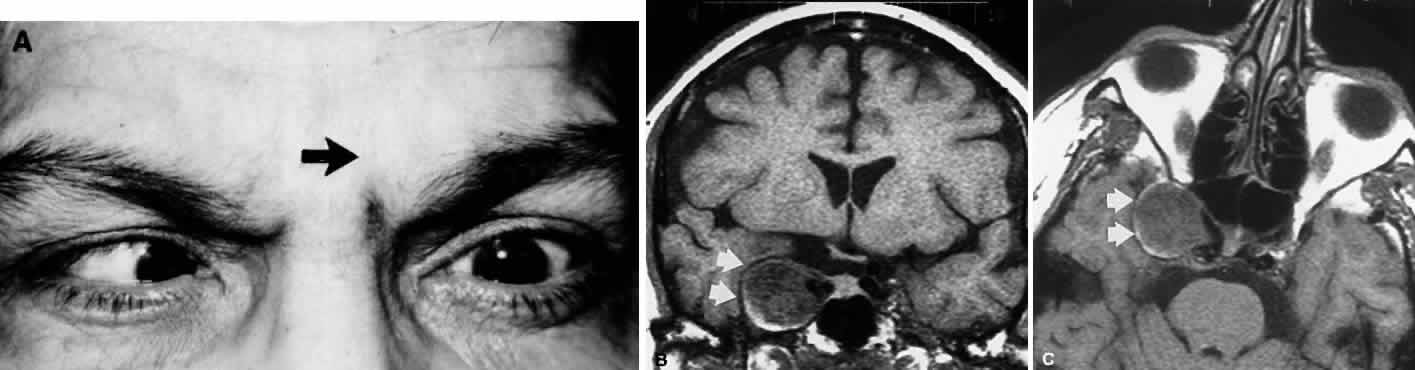

| Palsy of the superior oblique, as in the case of isolated lateral rectus

weakness, may be due to local orbital processes that should be distinguished

from a neurogenic lesion per se. As always, myasthenia and Graves

myopathy (an especially frequent cause of incomitant vertical strabismus) must

be suspected and appropriate tests performed. The pattern

of muscle imbalance and ocular versions can be quite similar in ipsilateral

inferior rectus fibrosis (e.g., in Graves disease) and contralateral superior oblique paresis50; however, worsening of the vertical deviation in upgaze is seen in inferior

rectus fibrosis, and in downgaze in superior oblique palsy. Also, intraocular

pressure may increase in attempted upgaze in restrictive (Graves) disease. Excyclodeviations are more prominent in superior oblique

paresis than in thyroid myopathy, which may show significant excyclotorsion

only in abduction. Superior oblique palsies may present spontaneously in late childhood and possibly represent “decompensated” congenital fourth nerve palsies. This diagnostic concept (i.e., that fusional mechanisms decompensate in later life) has also been applied to otherwise healthy adults with spontaneously acquired, unremitting superior oblique palsies of unknown origin (Fig. 9). A similar, often transient, occurrence of superior oblique palsy has been reported during pregnancy.51 These adults complain of reading difficulties, principally momentary diplopia, and show all of the attributes of superior oblique palsy. Old photographs may document tilting of the head, and further inquiry may uncover a forgotten history of childhood squint. Patients with congenital trochlear palsies commonly show increased amplitudes of vertical vergence.52 Normally, only 2 to 4 prism diopters (D) of vertical fusional amplitude are found, but patients with congenital superior oblique pareses may be able to fuse a 10-D or even a 30-D deviation. However, the presence of large vertical fusional amplitudes does not necessarily imply a congenital etiology, because vertical fusional vergence may increase in adults within weeks or months after an acquired vertical strabismus. The cause of most congenital superior oblique palsies is unknown; however, agenesis of the trochlear nucleus has been described in association with agenesis of other cranial-nerve nuclei,53 but never in the situation of an isolated congenital fourth nerve palsy. Dysplasia (aplasia) of cranial nuclei may occur after perinatal peripheral injuries to nerves, with secondary “dying back.” Also, axonal death, with selective elimination and preservation, is an established phenomenon during neurogenesis of all cranial nerves.54 Absence of the superior oblique tendon has been observed during surgery to correct putative isolated congenital superior oblique palsies. This phenomenon may be more common in patients with craniofacial dysostoses.55 Indeed, Helveston et al56 reported congenital absence of the superior oblique tendon in 18% of patients with congenital superior oblique palsy, in whom a tuck of the superior oblique had been contemplated, and in another subgroup of patients with congenital superior oblique pareses, abnormally lax superior oblique tendons have been described. Bilateral congenital superior oblique palsies (particularly asymmetric pareses), as with bilateral acquired superior oblique palsies, may initially appear to be unilateral until corrective surgery “unmasks” the contralateral palsy. Other than in the context of trauma, acquired isolated fourth nerve palsy occurs far less frequently than abducens or oculomotor palsies. In a retrospective study of 412 patients,57 third and sixth nerve palsies were seven times more common than fourth nerve palsy. As with isolated abducens palsy, many spontaneous trochlear palsies are classified as “unknown” or “vascular.” In the older age group, isolated fourth nerve palsy is frequently associated with diabetes. Keane58 provided an excellent overview of fourth nerve palsy among 215 patients, with head trauma representing the cause in more than 50%; no tumors showed isolated palsies, but were accompanied by other defects related to lesions in the cavernous sinus. In comparison, 149 patients with ocular myasthenia did not show isolated superior oblique palsies. Bilateral fourth palsies occurred in 19%; again, the majority of these cases were due to head trauma. Herpes zoster ophthalmicus may be associated with isolated trochlear palsy,59 with variable recovery, but meningitis produces other signs and symptoms.58 Although extremely rare, intracranial aneurysms (e.g., superior cerebellar artery) have been documented to cause superior oblique palsy as well.60 Autosomal-dominant inheritance of superior oblique palsy, some bilateral, is also documented.61 The causes of fourth nerve palsies are listed in Table 4.